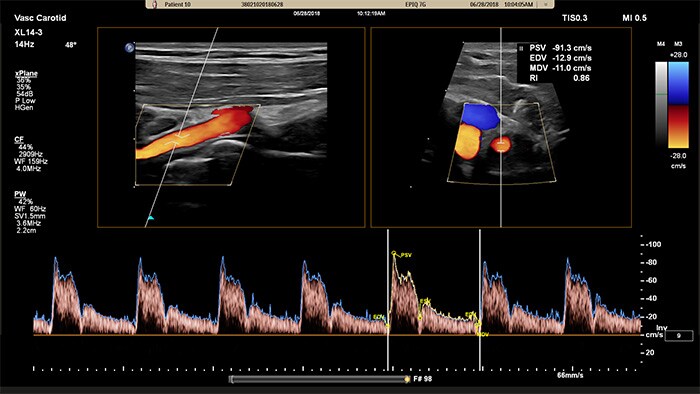

El transductor XL14-3 xMATRIX ofrece una adquisición de imágenes xPlane que supera al sistema convencional para exploraciones vasculares, pues ofrece imágenes en tiempo real tanto en los planos longitudinal como transversal de forma simultánea. La ventaja principal: las imágenes xPlane eliminan la necesidad de girar el transductor para adquirir vistas ortogonales. Basta con mover la esfera para realizar una evaluación anatómica completa, con lo que se ahorra tiempo en la exploración.

El XL14-3 xMatrix también ofrece funciones de Doppler xPlane. El Doppler pulsado xPlane permite una colocación precisa del volumen de muestra mediante Doppler a través de imágenes de referencia longitudinales y transversales. La principal ventaja: el Doppler xPlane reduce los errores de colocación del volumen de muestra y ofrece una mayor reproducibilidad y coherencia a la hora de tomar muestras de estenosis pronunciadas.